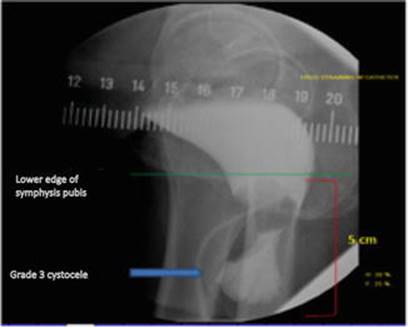

· VCUG: 600 mL bladder capacity with large cystocele Grade 3 and urethral hypermobility. No residual (Fig. 16.6).

Fig. 16.6

Lateral VCUG showing bottleneck appearance of a Grade 3 cystocele on straining with poorly supported urethra represented by the axis of the urethral Foley catheter